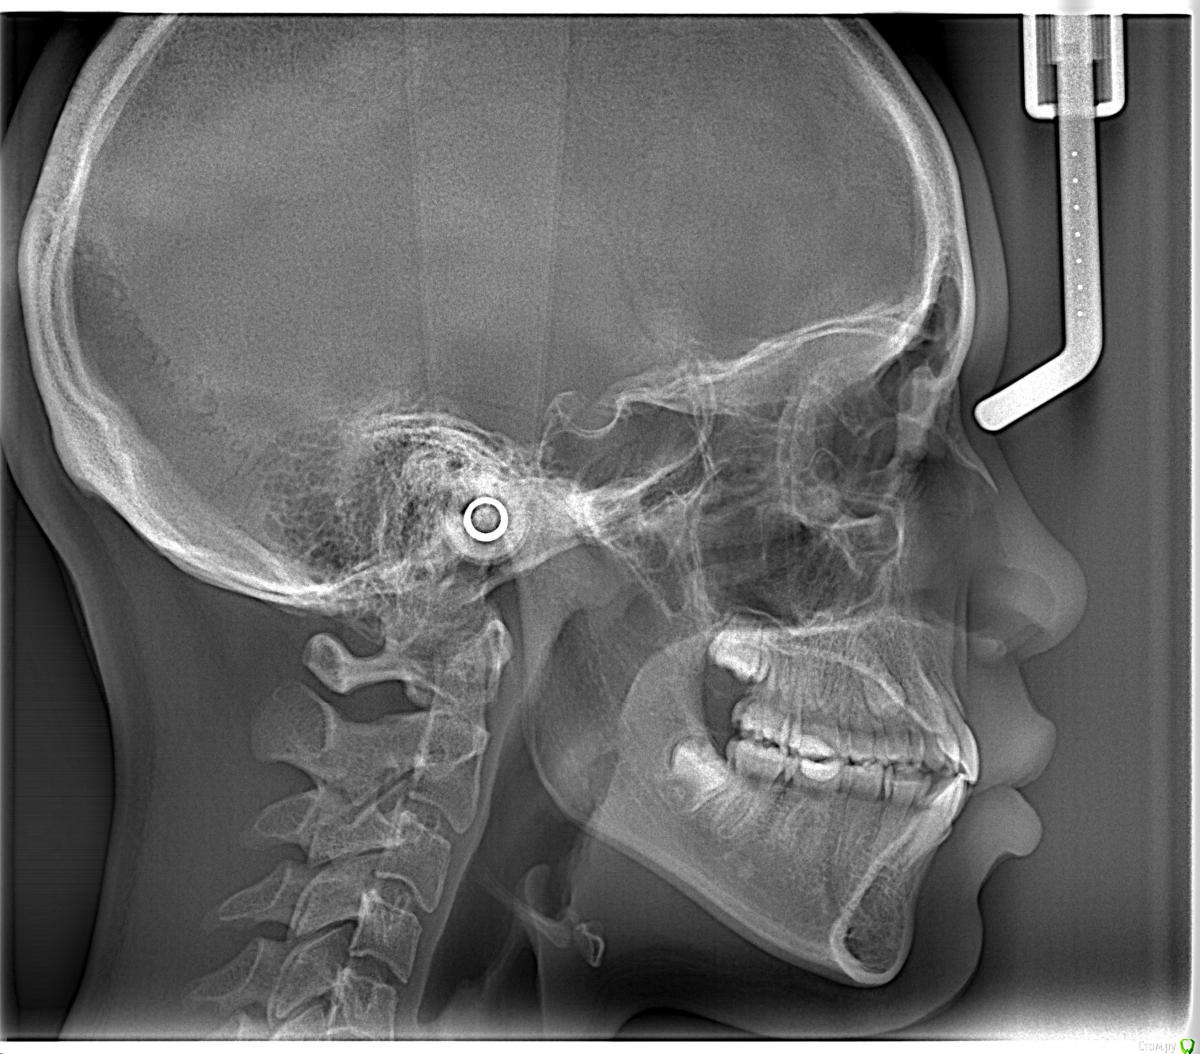

Opdihatop Опубликовано 20 февраля, 2017 Поделиться Опубликовано 20 февраля, 2017 Здравствуйте, коллеги! Вот такой вот случай третьего класса, вертикального роста, множественной первичной адентии и преинтереснейшего 13-го зуба. Девочке 14 лет. Сразу скажу, что вопреки некоторым классикам удалять клык или премоляры мы не будем, будем ставить в дугу, причем на его законное место. Может у кого-то были подобные случаи, поделитесь опытом, будьте добры. Какой план лечения и какая биомеханика тут будут самыми оптимальными? Заранее всем спасибо! Ссылка на комментарий

Opdihatop Опубликовано 20 февраля, 2017 Автор Поделиться Опубликовано 20 февраля, 2017 52, 53 молочные. 12, 22 - адентия. Клык пойдет на место 13. Когда-то на курсе Рафаэля Спены видел подобное, но, к сожалению не зафиксировал на фото. В общем и целом принцип помню. Но тут есть одно огромное НО... 14, 15 началась резорбция верхушек из-за 13 зуба, что видно по КТ. Ссылка на комментарий

Opdihatop Опубликовано 20 февраля, 2017 Автор Поделиться Опубликовано 20 февраля, 2017 (изменено) вот такая штучка еще в кости... Видел, на вид - простая остеомка, так что пугать пациента не буду, передвижению зубов не мешает. а про каких именно классиков Вы говорите? (это я для себя, для развития..) Вот простите, не вспомню, читал монографию какого-то итальянца еще на этапе обучения, так там было сказано вообще их удалять, особенно при транспозиции через ц.л. у ВАшей девочки я бы удаляла восьмерки, ставила винты в подскуловую область , часть зубов назад, а часть - пружинами вперед. создавая место. про клык - здесь конечно по КТ надо смотреть, куда его тащить и как открывать. Возможно лучше вначале открыть место (раздвинуть 5ку и 4ку) а потом клык поставить между ними. Клык станет 4кой а 4ка клыком. (имхо) Подскуловые импланты, это классно, только вот в Украине этих корейцев не продают пока (Диаметра не хватает и длины). Дистализирую пружинами при непрямом анкораже на микроимплантате между 5 и 6. Как я собирался тянуть клык вперед? На 14, 15 ставятся брекеты от нижних премоляров и ставятся они на толстую композитную подушку, которая постепенно утолщается. Таким образом зубы постепенно уходят орально, а их корням придается небный торк, освобождая путь в кости для 13. Затем при помощи компактостеотомии быстро мезиализируется 13, затем 14 и 15 плавно перемещаются назад (хотя 15 это вряд ли коснется... его я планирую перед этим дистализировать). Сам я такое не делал, но видел на курсе. Вот, выпал шанс попробовать. Зачем? Во-первых, научный интерес, во-вторых, родители категорически против ремоделирования коронок зубов... Изменено 20 февраля, 2017 пользователем Opdihatop Ссылка на комментарий